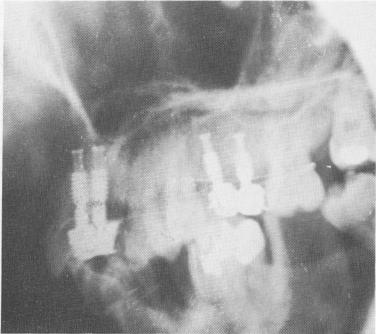

The crowns were cemented over the two protruding implant shafts in the same manner as in Case 1 (Fig. 8-14). However, whereas the implants in Case 1 were left completely unsplinted from the very onset, in this case the implants were immediately ligated to neighboring teeth with soft .010 stainless steel ligature wire (Fig. 8-15). The occlusion once again was carefully checked and all necessary adjustments were made (Fig. 8-16). A post-operative lateral plate roentgenogram of the completed case shows all implants in place (Fig. 8-17).

Fig. 8-17. A lateral plate roentgenogram illustrating the implants.